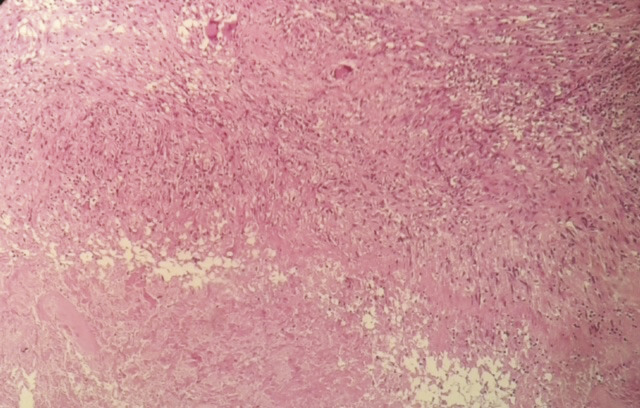

Ce patient de 48 ans, tabagique chronique (25 paquets-années), avait depuis 1 mois une tuméfaction parasternale droite fluctuante en son centre, avec une peau inflammatoire en regard. L’échographie des parties molles montrait une collection hétérogène et hypoéchogène au niveau de la paroi thoracique antérieure droite. La tomodensitométrie thoracique montrait un processus lésionnel pariétal parasternal droit mesurant 68 x 35 x 28 mm en continuité avec un foyer pulmonaire droit (fig. 1 ). Le bilan biologique montrait un syndrome inflammatoire, avec une protéine C-réactive à 56 mg/L, des lymphocytes à 12 500 éléments/mm3 ; la recherche de bacilles de Koch dans les expectorations et dans le liquide de ponction de la collection pariétale était négative à l’examen direct. La biopsie mettait en évidence des granulomes épitélioïdo-giganto-cellulaires avec nécrose caséeuse (fig. 2 ). La sérologie du VIH était négative, et le patient mis sous traitement antituberculeux pendant 6 mois, avec une bonne évolution clinique et radiologique.